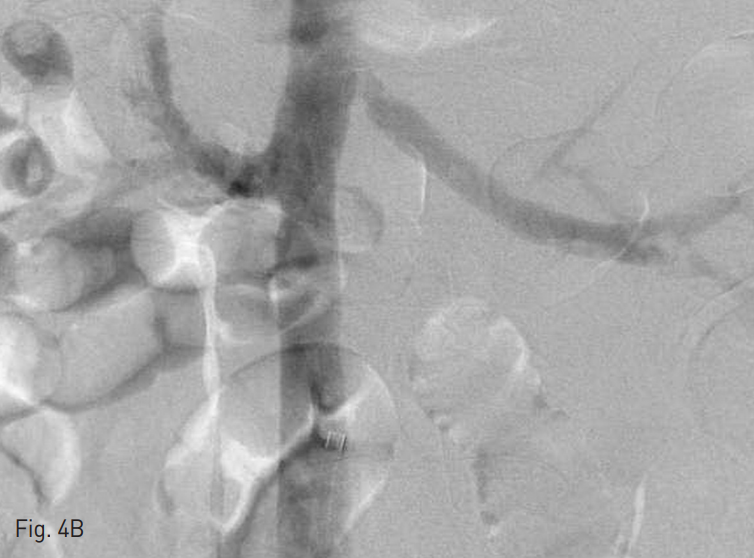

Fig. 2

Infrahepatic IVC is obstructed due to thromobosis, on inferior vena cavogram.